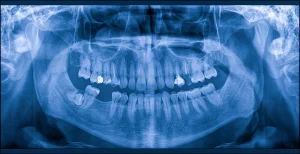

口の中に小さなフィルムやセンサーを入れて撮影する口内法レントゲンと、顔の外側から広範囲を撮影するパノラマレントゲンがあり、口内法レントゲンでは虫歯の進行度や歯の根の状態、歯周病による骨の吸収などを診断することができます。

パノラマレントゲンは、上下の歯列全体と顎骨を一枚の画像で確認できるため、口腔内の全体的な状態把握や親知らずの位置確認などに用いられます。